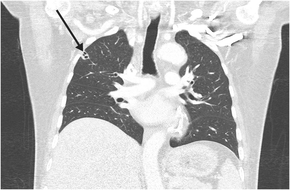

His clinical course was complicated by septic thromboembolism, including left renal vein thrombosis, multi‐territorial subcortical strokes, and disseminated lung infection, with multiple peripheral cavitating nodules (Box 3). Transoesophageal echocardiogram and cardiac magnetic resonance imaging showed no evidence of infective endocarditis or patent foramen ovale.